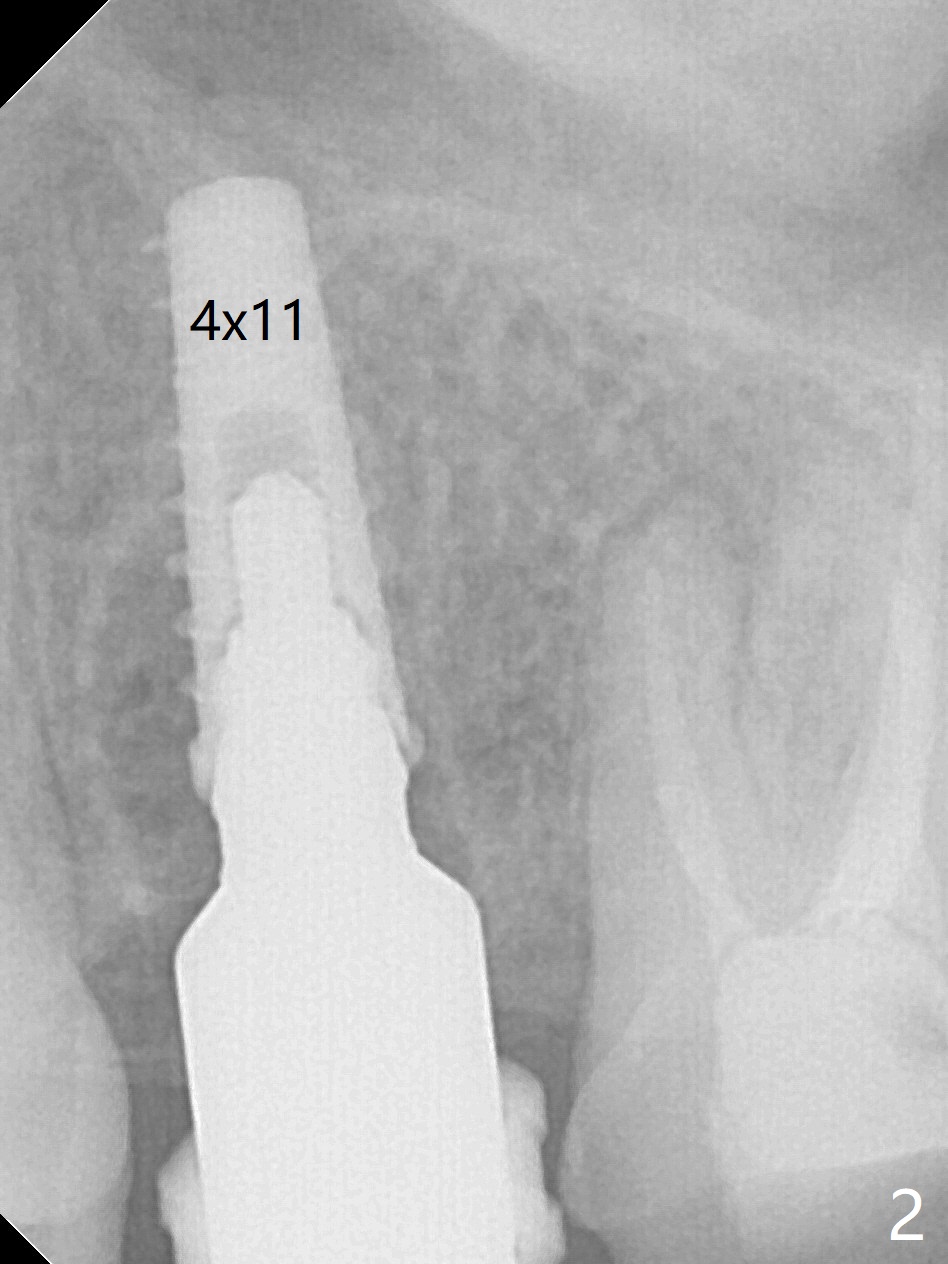

Due to misinterpretation of drill sequence, osteotomy is overprepared in depth (1.5 to 3 mm). When a 4x11 mm dummy implant is placed with > 50 Ncm (Fig.1,2), over placement is ignored. A 4x13 mm final implant is placed with fairly good torque, but it is deeper than expected. When it is backed up, primary stability is lost, in spite of placement of allograft in the osteotomy. Final torque is 15 Ncm. When a 4.5x4(2) mm abutment is placed, the underlying implant turns (Fig.3). A splinted provisional is fabricated at #13 and 14. RCT is retreated 5 months postop (Fig.4 *). An abutment with longer cuff is placed before impression (8.5 months postop, Fig.5). When the crowns of #13 and 14 are delivered, the former looks short and noncosmetic, although the gingiva will grow downward to close the gap (Fig.6). Ideally the gap should be closed with porcelain with overhang (Fig.7).